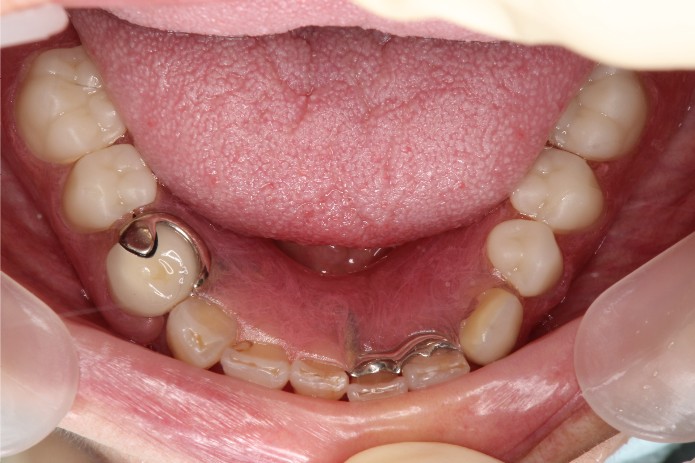

43歳のSさんはある歯科医院で抜歯(歯を抜く)をしてインプラントを入れるか総入れ歯にするしかないと言われました。

その医院では初めから歯を残そうという選択枝はなかったとおっしゃっていました。

歯が全部無くなってしまうという喪失感は、まだ若いSさんにとっては大きなものです。

その思いがせめて歯の根は抜かずに、根の上に入れ歯をのせるということになったそうです。(上段の写真)

しかしこのままではいずれ本当に歯が全部無くなってしまう。

そのことを何とか回避したい。そんな思いで来院されたました。

検査、診断、病状把握の結果、上の前歯はすべて残すことが可能であることがわかりました。

歯周病、ムシ歯、感染根管、咬合(咬み合わせ)などすべての問題を解決し、

やっと40歳代の女性の笑顔を取り戻すことができました。(下段の写真)。